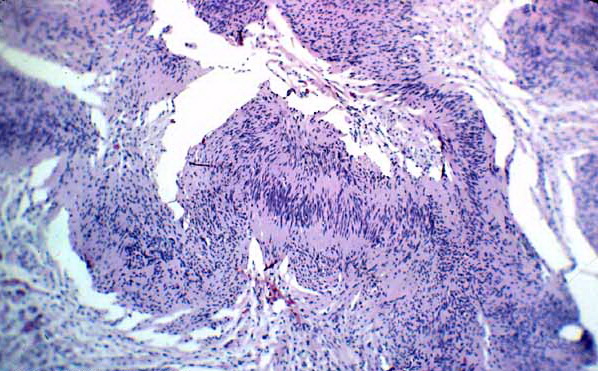

Necrobiois lipoidica diabeticorum = النخر الشحماني السكري Necrobiosis Lipoidica Necrobiosis lipoidica is an idiopathic disorder typified by indurated plaques of the shins . In 1966, in a large series, Muller and Winkelman reported that two thirds of patients with necrobiosis lipoidica had overt diabetes at the time of diagnosis {82}. Of the rest, all but […]